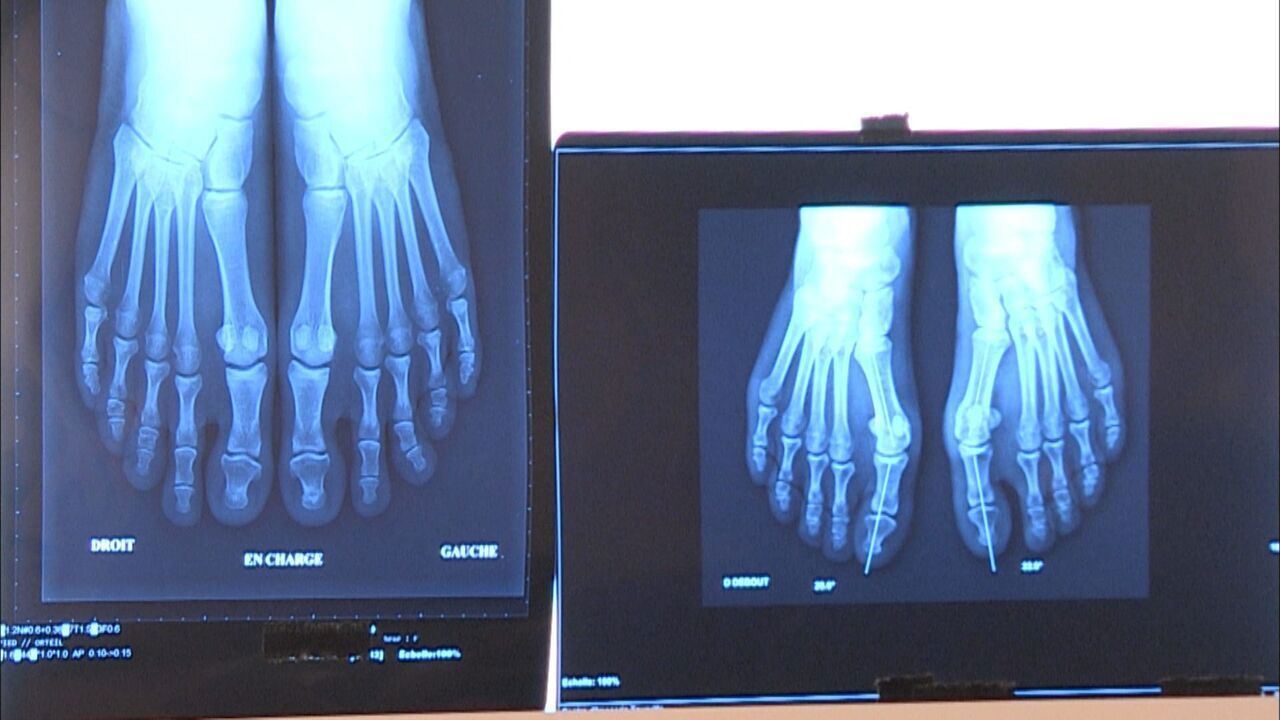

Mortonov nevrom – vzroki, simptomi in rehabilitacija